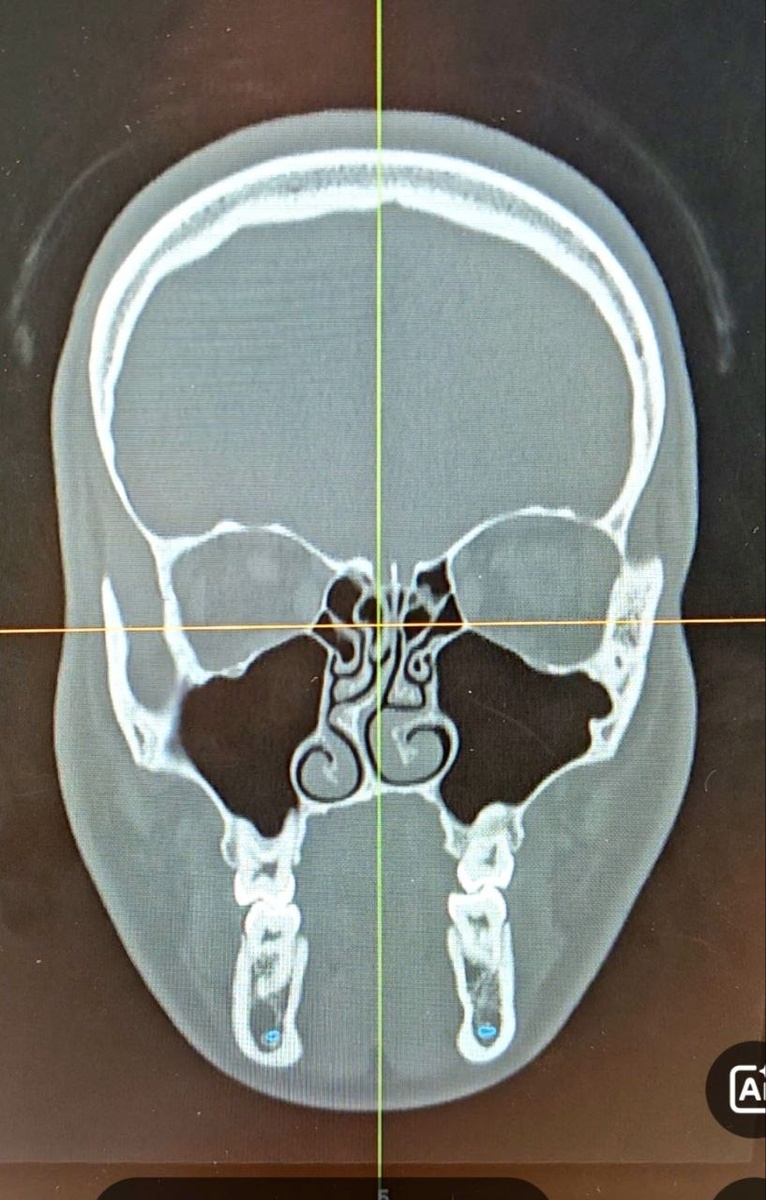

Результат на столе - функциональная риносептопластика кривого носа с грубой деформацией перегородки

Результат на столе - функциональная риносептопластика кривого носа с грубой деформацией перегородки.